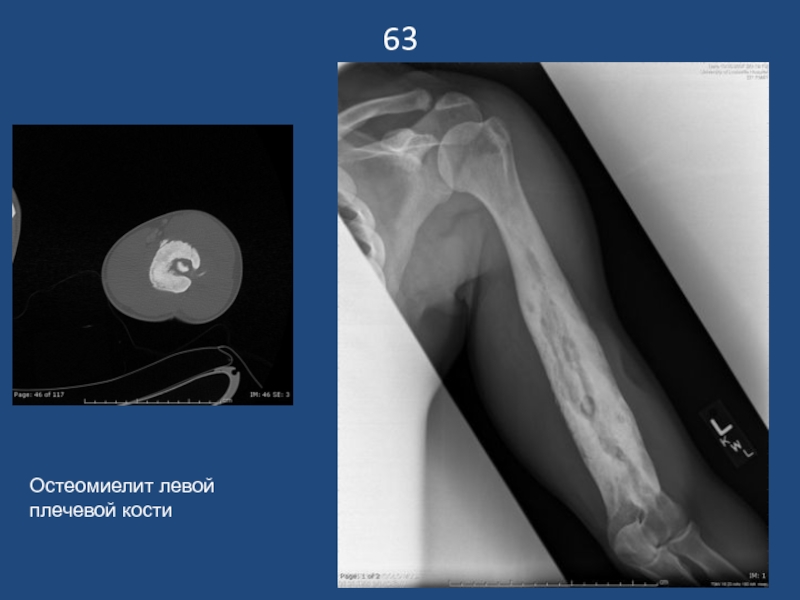

Слайд 6463

Остеомиелит левой плечевой кости

63Остеомиелит левой плечевой кости